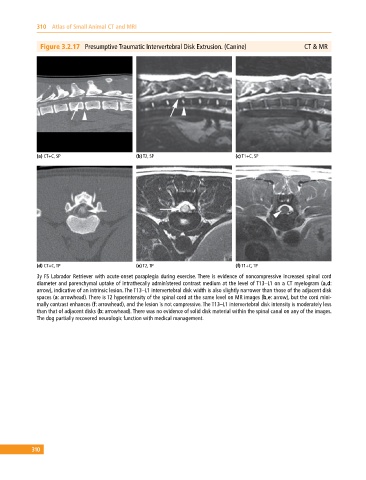

Figure 3.2.17 Presumptive Traumatic Intervertebral Disk Extrusion. (Canine) CT & MR

(a) CT+C, SP (b) T2, SP (c) T1+C, SP

(d) CT+C, TP (e) T2, TP (f) T1+C, TP

3y FS Labrador Retriever with acute‐onset paraplegia during exercise. There is evidence of noncompressive increased spinal cord

diameter and parenchymal uptake of intrathecally administered contrast medium at the level of T13–L1 on a CT myelogram (a,d:

arrow), indicative of an intrinsic lesion. The T13–L1 intervertebral disk width is also slightly narrower than those of the adjacent disk

spaces (a: arrowhead). There is T2 hyperintensity of the spinal cord at the same level on MR images (b,e: arrow), but the cord mini-

mally contrast enhances (f: arrowhead), and the lesion is not compressive. The T13–L1 intervertebral disk intensity is moderately less

than that of adjacent disks (b: arrowhead). There was no evidence of solid disk material within the spinal canal on any of the images.

The dog partially recovered neurologic function with medical management.